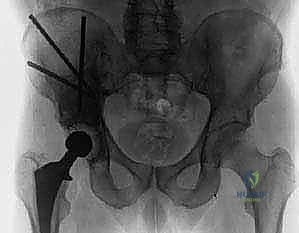

في عيادات الأستاذ الدكتور محمد هطيف في صنعاء، يتم اتباع بروتوكول تشخيصي صارم وشامل لتحديد حجم المشكلة وتقييم الخطر الحقيقي للكسر. يشمل هذا البروتوكول:

- الأشعة السينية العادية (X-rays): الخطوة الأولى والأساسية. تظهر تدمير العظم (الآفات الحالّة) أو زيادة الكثافة غير الطبيعية (الآفات التكوينية).

- التصوير المقطعي المحوسب (CT Scan): يوفر صوراً ثلاثية الأبعاد تفصيلية للعظام. يعتبر الأداة الأهم لتقييم مدى تدمير العظم القشري (الطبقة الخارجية الصلبة) وتخطيط حجم ونوع المفصل الاصطناعي بدقة.

- اختيار نوع المفصل الاصطناعي: بناءً على صور الأشعة المقطعية، يحدد الجراح نوع المفصل. في حالات الأورام، غالباً ما تُستخدم مفاصل ذات جذوع طويلة (Long-stem prostheses) لتجاوز منطقة الورم وتثبيت المفصل في العظم السليم أسفل الآفة. كما تُستخدم تقنية الأسمنت العظمي (Bone Cement - PMMA) بكثافة لتوفير استقرار فوري للمفصل والسماح للمريض بالمشي في اليوم التالي.

* إذا كان التدمير كبيراً، يستخدم الدكتور هطيف دعامات معدنية خاصة (Reconstruction Rings/Cages) يتم تثبيتها بمسامير في عظام الحوض السليمة لإنشاء سقف جديد للمفصل.

- في مرضى السرطان النقيلي، يُفضل استخدام الأسمنت العظمي لتثبيت الجذع. الأسمنت العظمي لا يعمل كصمغ فقط، بل كحشوة تملأ الفراغات التي تركها الورم وتوفر دعماً ميكانيكياً فورياً.